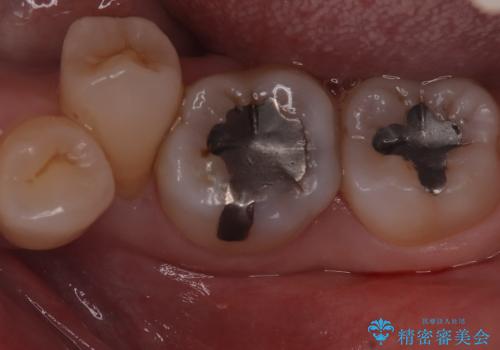

- 主訴:口を開けると所々入っている銀の詰め物が目立つので白い物にやり替えたい。

下顎大臼歯部に入っている保険適用のメタルインレーを、適合性と審美性の良いセラミックインレーでのやり替えとなりました。

メタルインレーを除去した際、古い裏層材やカリエスは除去し新たにCR裏層しています。